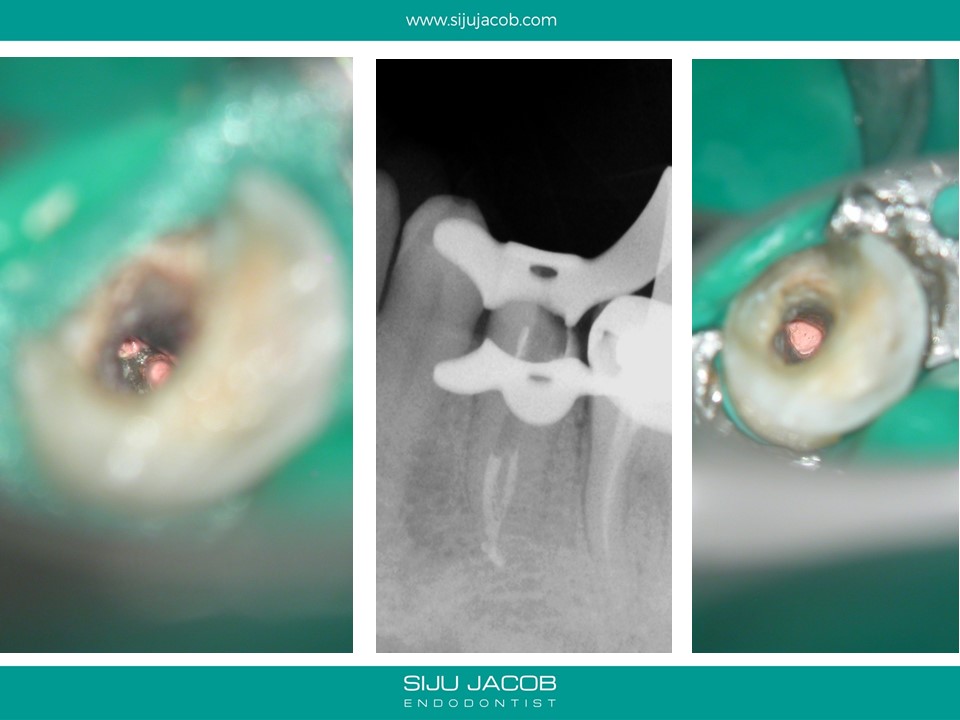

Previous clinician started this case and referred it when the patient continued to have pain. This was a two-rooted mandibular pre-molar with the canals present at a very odd angle and position. It was difficult to clean, shape and pack because the canals were very close to each other. When obturating these canals, I usually down pack one canal, then use a small micro-opener to remove the G.p that usually blocks the second canal and then down pack the second canal.